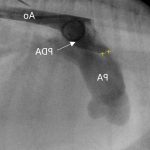

Understanding Patent Ductus Arteriosus in Dogs: Symptoms, Diagnosis, and Treatment

Learn about Patent Ductus Arteriosus in dogs, its symptoms, diagnosis, treatment options, and how to ensure your furry friend lives a healthy, happy life.